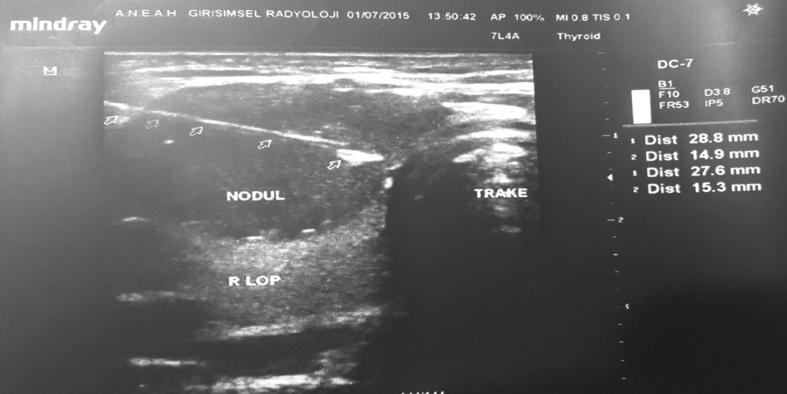

In this study-a retrospective analysis of FNAB via USG - our aim is to evaluate the multiple variables related to FNAB procedures, including the experience of the person performing the biopsy, the age and gender of the patient, the number of nodules, the size of the nodule(s) and the number of lams recorded from the cytopathology report on non-diagnostic rates, conducted at an invasive radiology clinic and at a general surgery clinic.

A total of 1062 patients involving 1869 nodules, examined using FNAB via USG, were reviewed retrospectively from records dated between November 2011 and July 2014 and from pathology reports taken from the ANEAH General Surgery clinic and Interventional Radiology clinic. Cytopathology results were classified according to the 2007 Bethesda System for Reporting. Gender, age, number of nodules, diameter of the nodules, biopsied nodules, location of the nodules, number of lams, symptoms and the date of biopsies were the parameters used to examine the factors involved in non-diagnostic cytopathology invasive radiology. These parameters were inspected at both of the clinics (ANEAH General Surgery clinic and Interventional Radiology clinic). In analyzing the results, the statistical significance level was set at 0.05, where in cases that the p value was under 0.05 (p < 0.05), it was determined that no significant relationship existed. In this study, data were analyzed using SPSS 20 software.